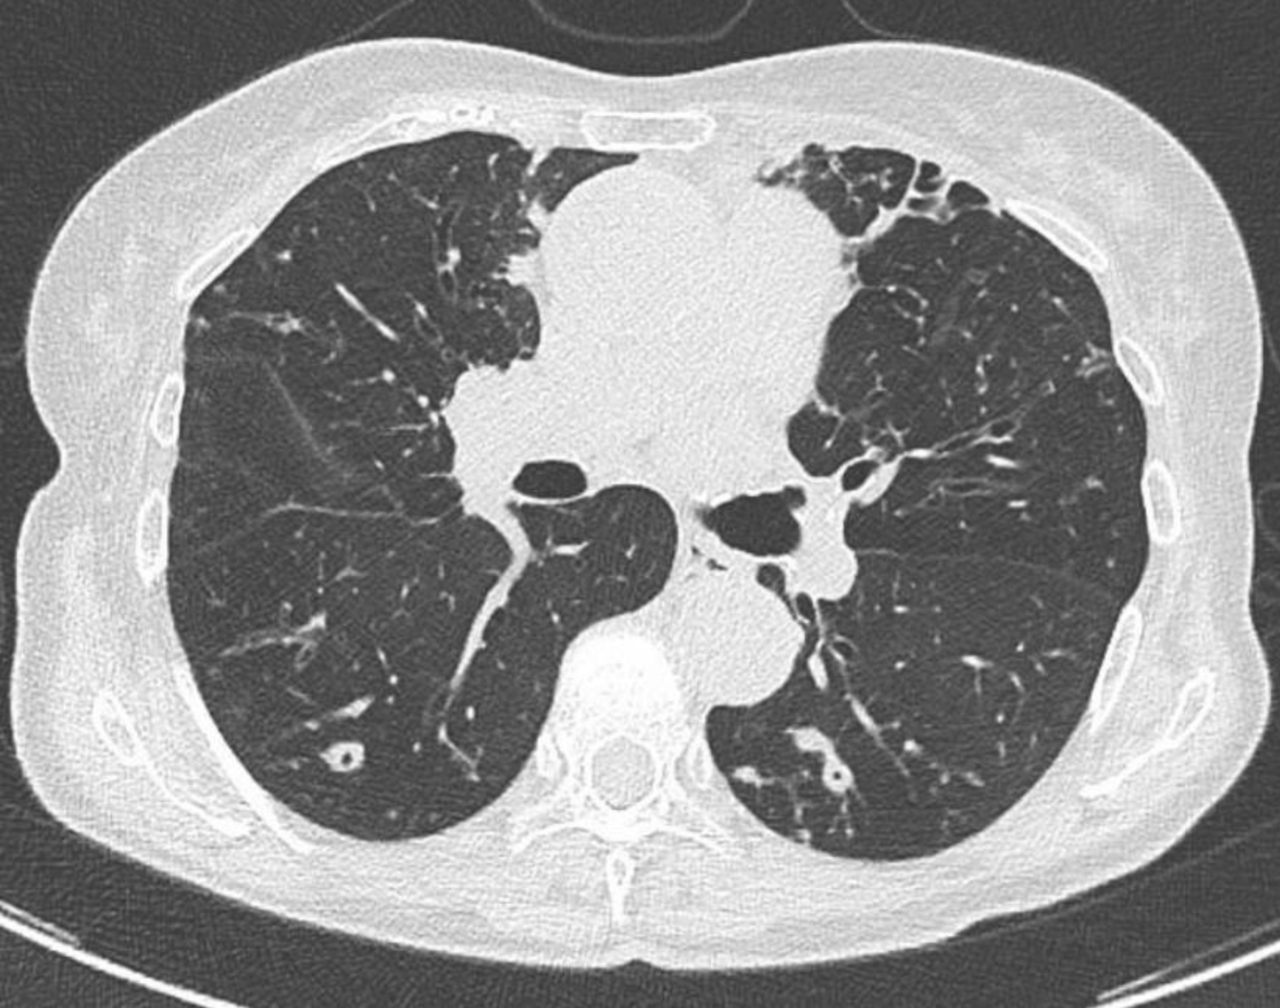

Vous réalisez donc les examens complémentaires suivants : – ETT sans anomalie notable – notamment pas de lésion valvulaire identifiée ; – fond d’œil sans foyer de rétinite ; – charge virale sérique CMV négative. Charge virale sérique EBV à 1,5 log ; – PCR nasopharyngée SARS-CoV-2, influenza et virus respiratoire syncytial (VRS) négative. Vous réalisez une TDM-TAP injectée qui ne retrouve pas d’anomalie notable à l’étage sous-diaphragmatique, notamment pas de foyer profond ni de polyadénopathie. Pas de lésion parenchymateuse hépatique ou splénique. À l’étage thoracique, vous identifiez en revanche ces lésions : Figure (Julien Derdevet, La Revue du Praticien)

La présence de nodules pulmonaires chez un sujet immunodéprimé – en dehors des causes tumorales – peut faire évoquer plusieurs étiologies infectieuses – bactériennes (Cocci à Gram positif ou germes intracellulaires, mycobactéries typiques (M. tuberculosis) ou atypiques, nocardiose...), fongiques (aspergillose, mucormycose, cryptococcose, histoplasmose, coccidioïdomycose...) voire virales. L’examen diagnostique le plus rentable reste donc dans cette situation le LBA. Plusieurs examens non invasifs peuvent toutefois être au préalable réalisés : l’antigénémie sérique galactomannane permet de diagnostiquer une infection à Aspergillus spp. (seul ou en faisant le rapport LBA/sérum), la PCR mucorale sérique a une très bonne valeur diagnostique pour les mucormycoses... Idem pour l’antigène cryptocoque sérique. Le bêta-D-glucane – marqueur antigénique pour presque toutes les infections fongiques en dehors de la cryptococcose et des mucormycoses – serait en revanche ici peu utile, puisque probablement positif dans le contexte de candidémie récente. Il a par ailleurs une cinétique de décroissance lente, ce qui en fait un mauvais marqueur pour le suivi thérapeutique. Enfin, il faut noter que les réactifs sont obtenus à partir d’extraits (sang) de limules – une espèce en déclin de par sa surexploitation. Pour finir, si une réactivation d’une tuberculose latente vers une tuberculose maladie reste possible – surtout chez un sujet né avant les années 1970 – les tests IGRA ou intradermoréaction (IDR) restent de peu d’utilité pour différencier ces deux cadres nosologiques.